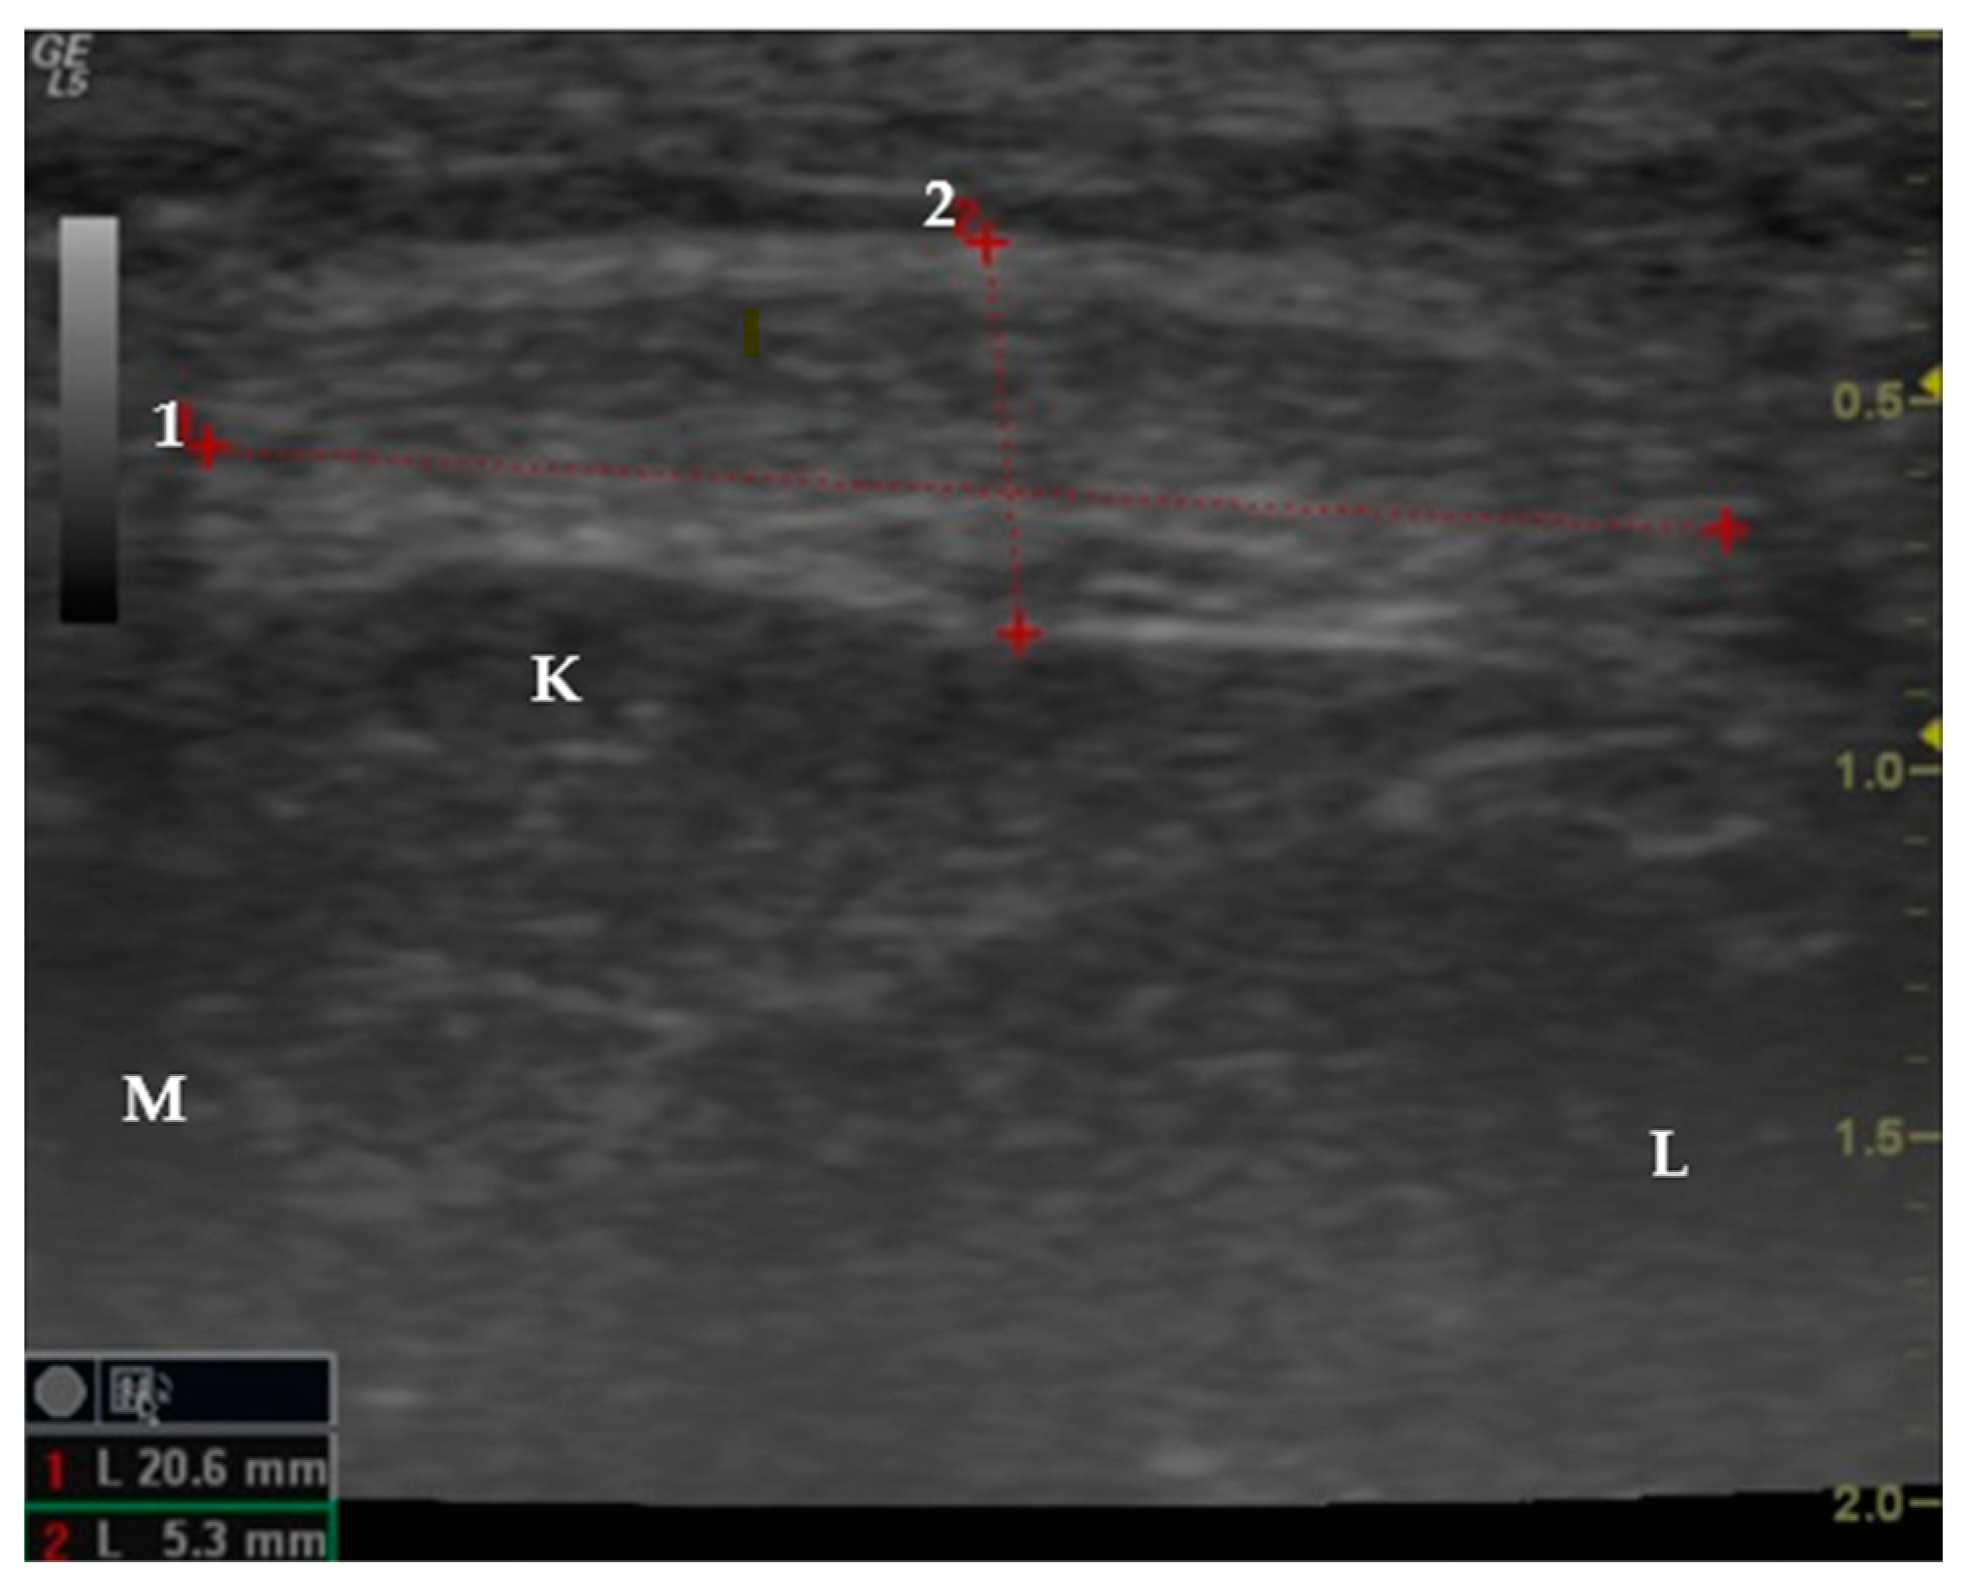

2.2. Study Design

2.3. Data Collection